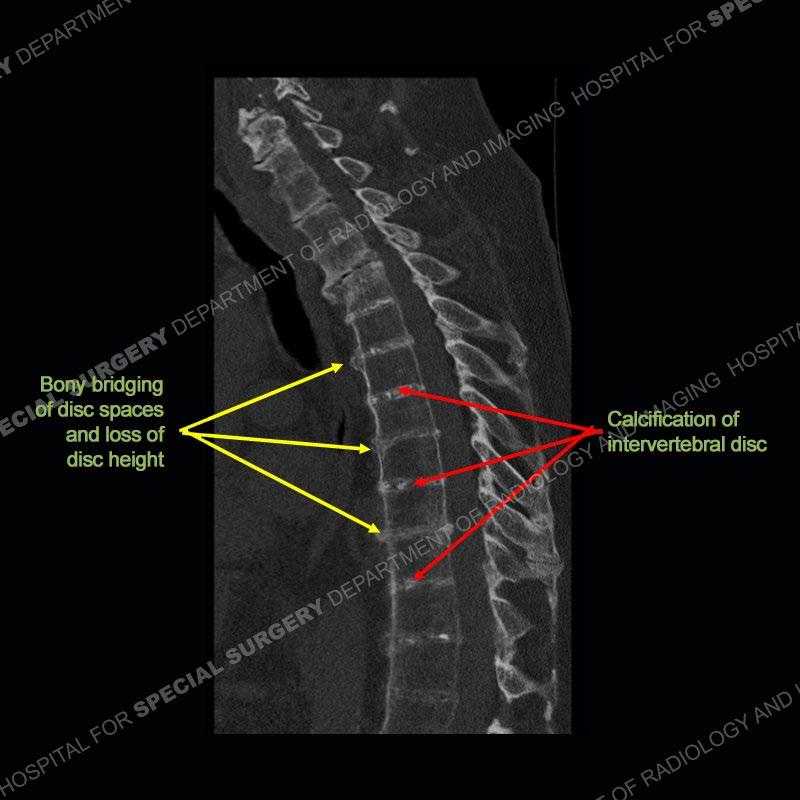

There is severe degenerative change of the left hip. The lumbar and thoracic spine show calcification of the intervertebral discs, loss of disc space, and bulky bony bridging across the disc spaces. Of important note is that the sacroiliac joints are open. They show advanced degenerative changes but not findings of an inflammatory arthritis. Bilateral knee arthroplasties are present and there are severe degenerative changes of both glenohumeral joints.

A rare metabolic disease also termed alkaptonuria. It results from a lack of homogentistic acid oxidase which results in a build up of this metabolite which gets deposited and oxidized in multiple tissues including, cartilage, synovium and bone. The soft tissues of the joint inclusive of the cartilage and the synovial fluid can be stained a black color or be densely black. Additionally, the urine can be stained black accounting for the term alkaptonuria. These patients frequently present with early onset osteoarthritis of multiple joints. There is classically calcification of the discs and a loss of disc space height. As patients get older, there may be bony bridging across the disc spaces as bulky paravertebral osteophytes.

In comparison to ankylosing spondylitis (AS) where there are thin syndesmophytes of the outer annulus, this bony bridging tends to be bigger and bulkier. In addition, at this stage of AS the sacroiliac joints would be fused, but in ochronosis as seen here, the SI joints are open although with severe degenerative changes. No erosions are present of the SI joints, just advanced degenerative changes. This patient was treated with a left total hip arthroplasty and the black deposition of oxidized homogentistic acid of the cartilage is well shown.